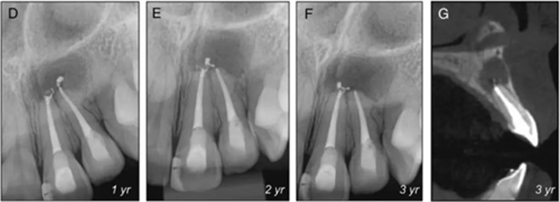

圖4. 根管治療后隨訪3年,根尖周透射影無變化,建議患者行根尖手術(shù)